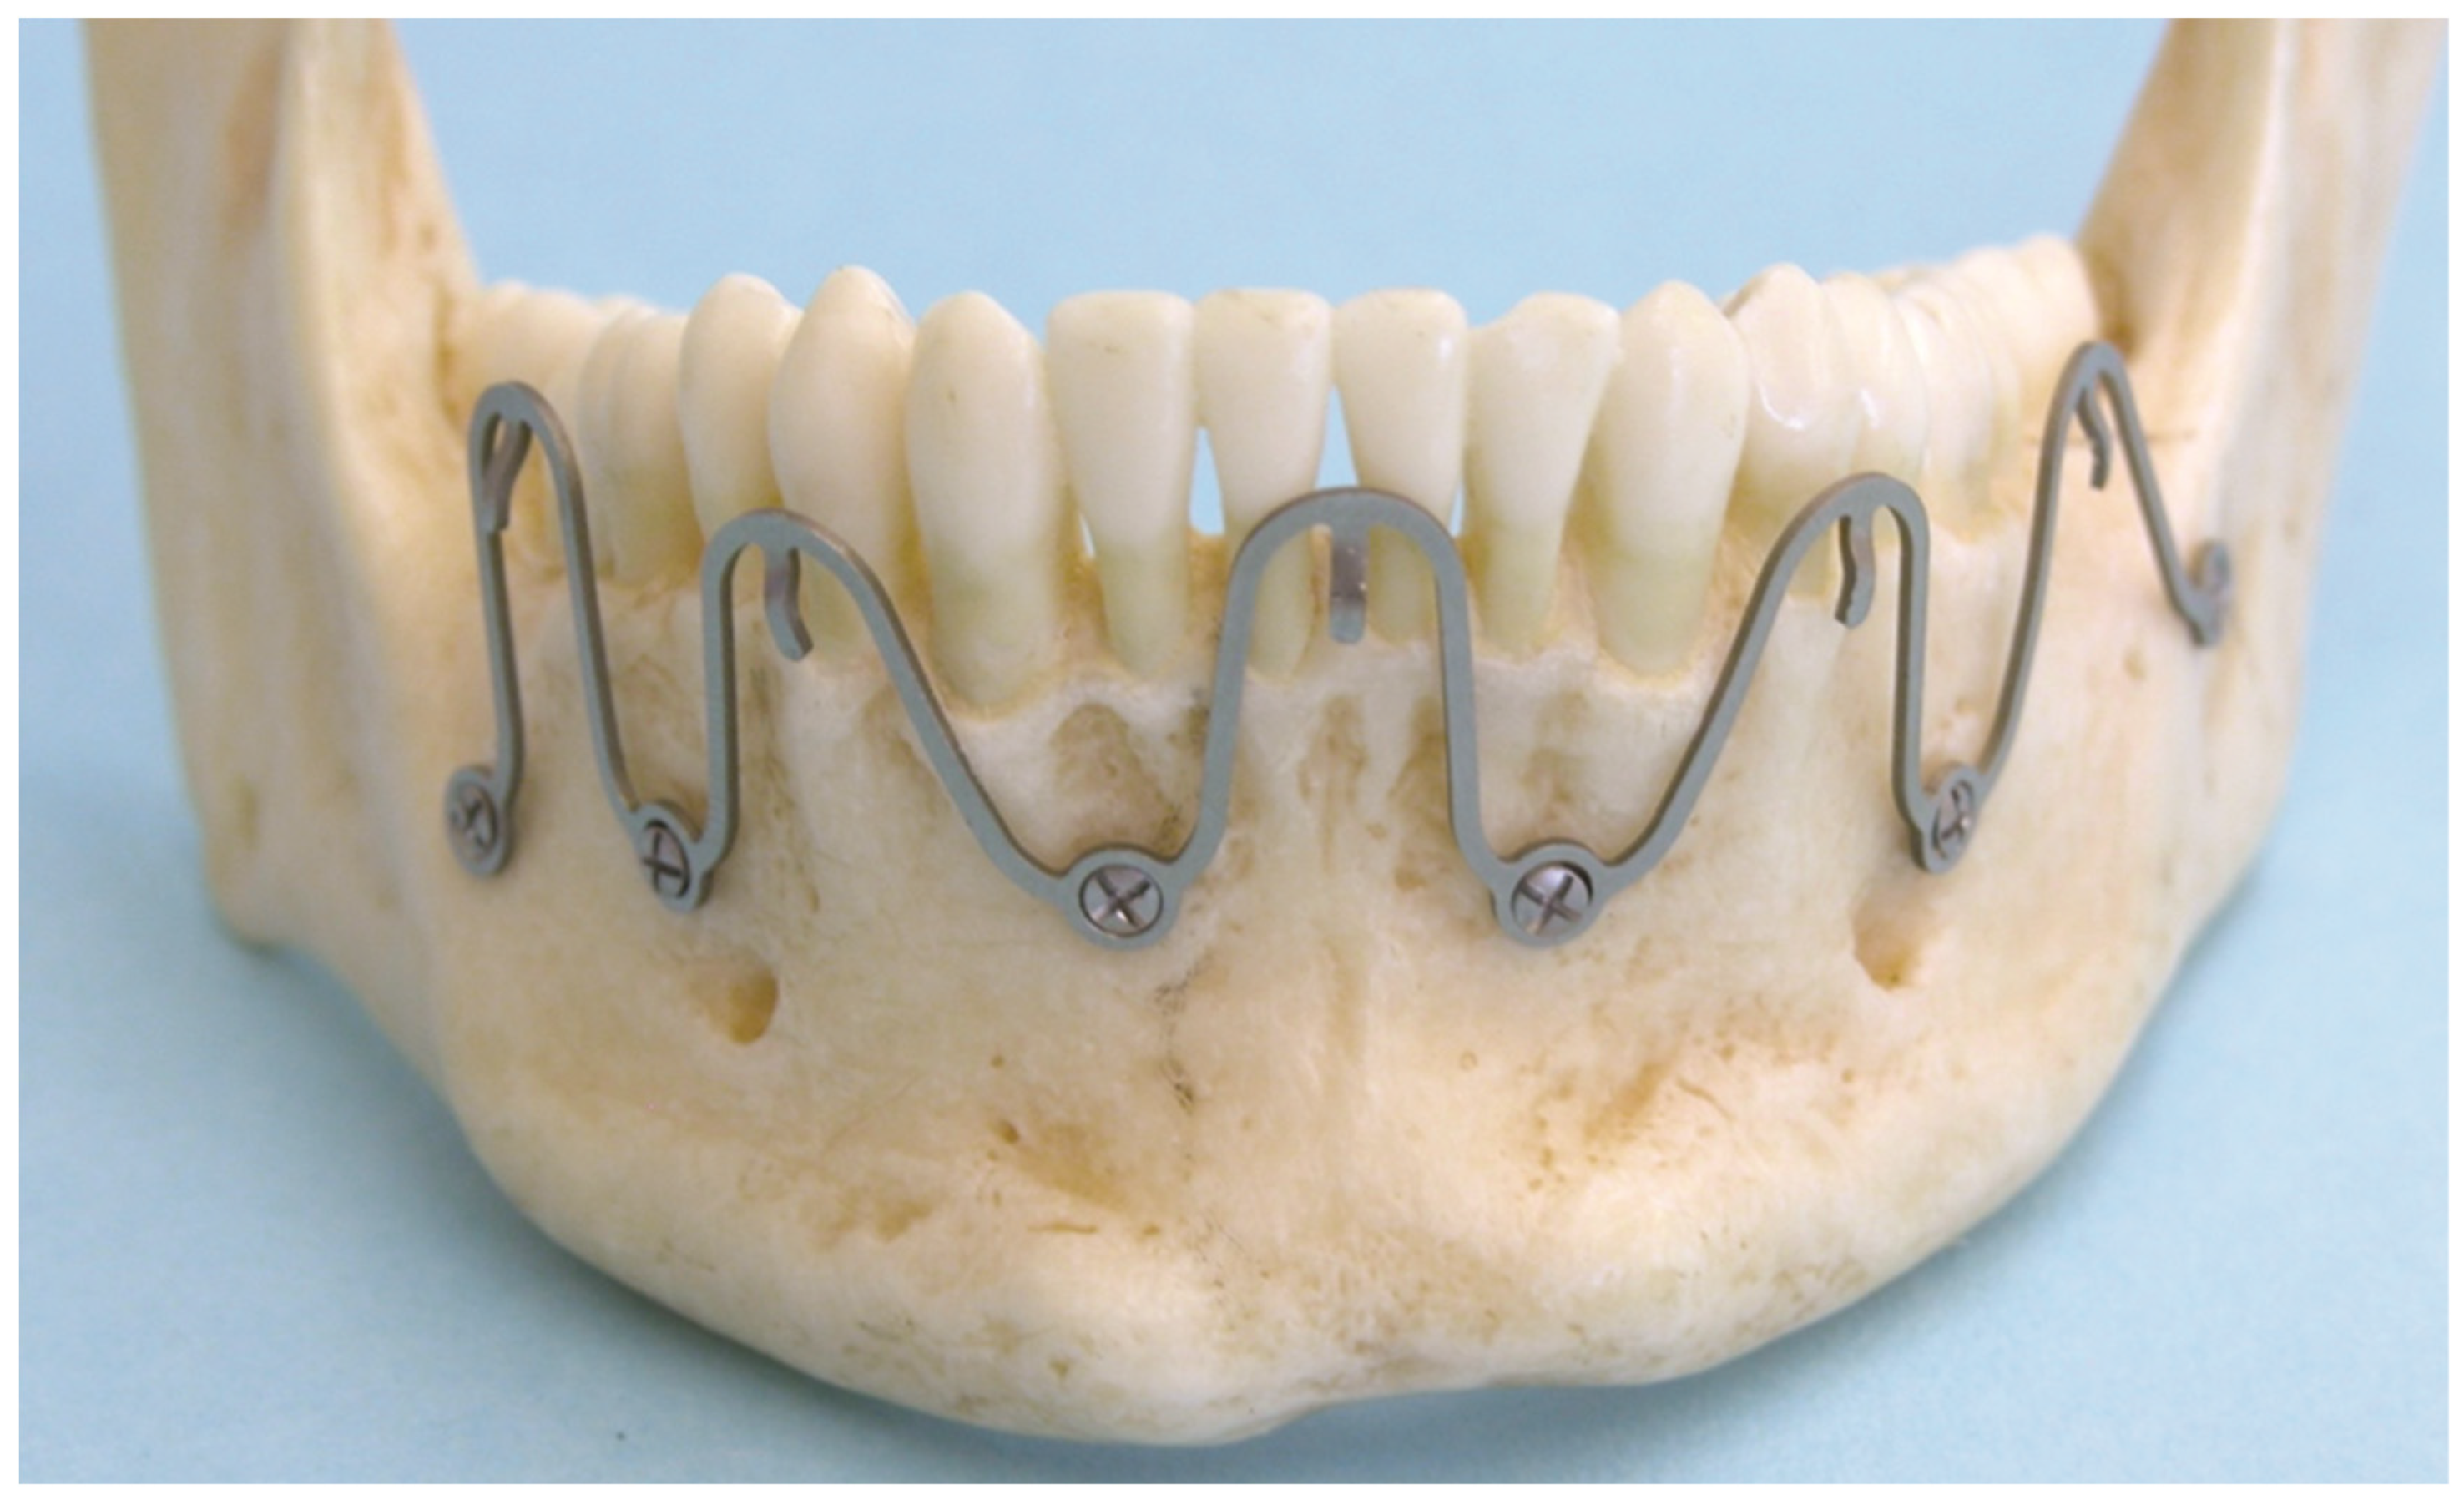

2.2. Predecessor—First-Wave Plate Version

2.3. Matrix Wave System—Final Design and Technical Description

3.1. Matrix Wave Plate—Segmentation and Malleability